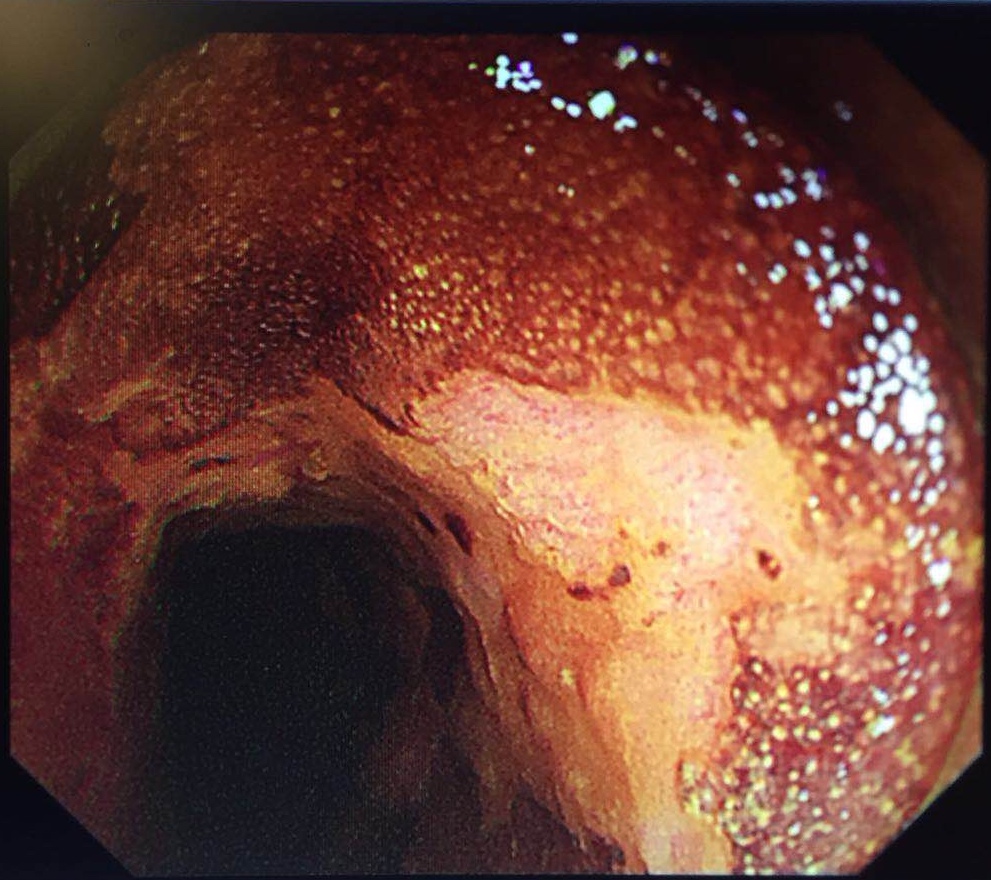

与此同时,北京协和消化疾病及消化内镜国际论坛暨第25届北京协和医院消化疾病与消化内镜研讨会在北京举行,国内外五十余位专家、五百余位代表参会。梁玮主任受邀作手术演示,完美演绎了一例病灶长达200px近环周的高难度早期食管癌“梁式ESD”治疗,向国内外同仁展示出精湛、创新的福建消化内镜技术,赢来阵阵喝彩。